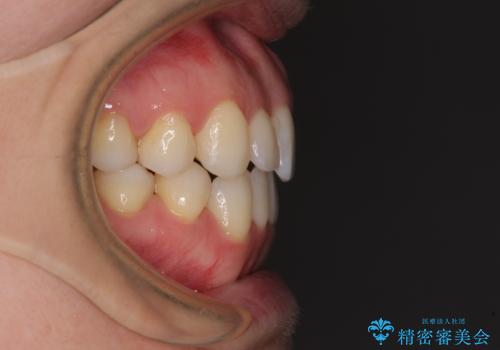

前歯の叢生とオープンバイト インビザラインでの矯正治療

- 前歯の開咬を気にして来院された患者様です。

開咬の治療は、前歯を閉じるように動かすとともに、上下臼歯を圧下(骨内にめり込ませる)させることで進めて行きます。

インビザラインは臼歯の圧下を効果的に行えるため、インビザラインを用いて矯正治療を行うこととしました。